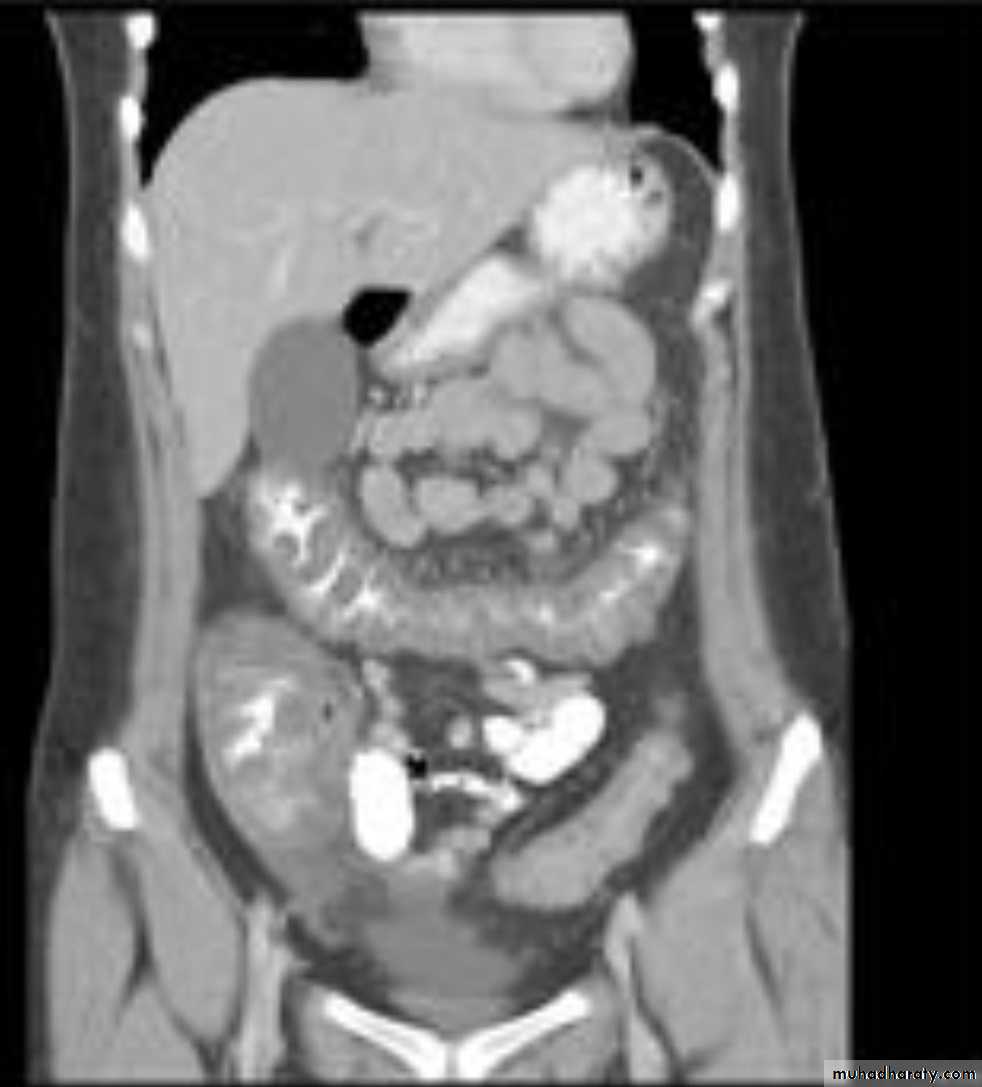

apple core lesion in the descending colon

Multiple lesions are seen in the liver and spleen consistent with metastases

Ba enema

• Morphological types:• 1_ Ulcerative : give rise to irregularity of the colon with ulceration.

• 2_ Constrictive or infiltrative ( Annular ) type :

• a- Constant narrowing .

• b-Shouldering sign, apple core sign .

• c- Destruction of mucosa at narrow area .

• d- Double track due to fistula .

• e- In severe constriction ; stoppage of Ba. Flow with proximal dilatation .

3_Proliferative type : give rise to :

a- Large , constant filling defect with irregular margin .

b- Destruction of mucosa .

c- Intestinal obstruction